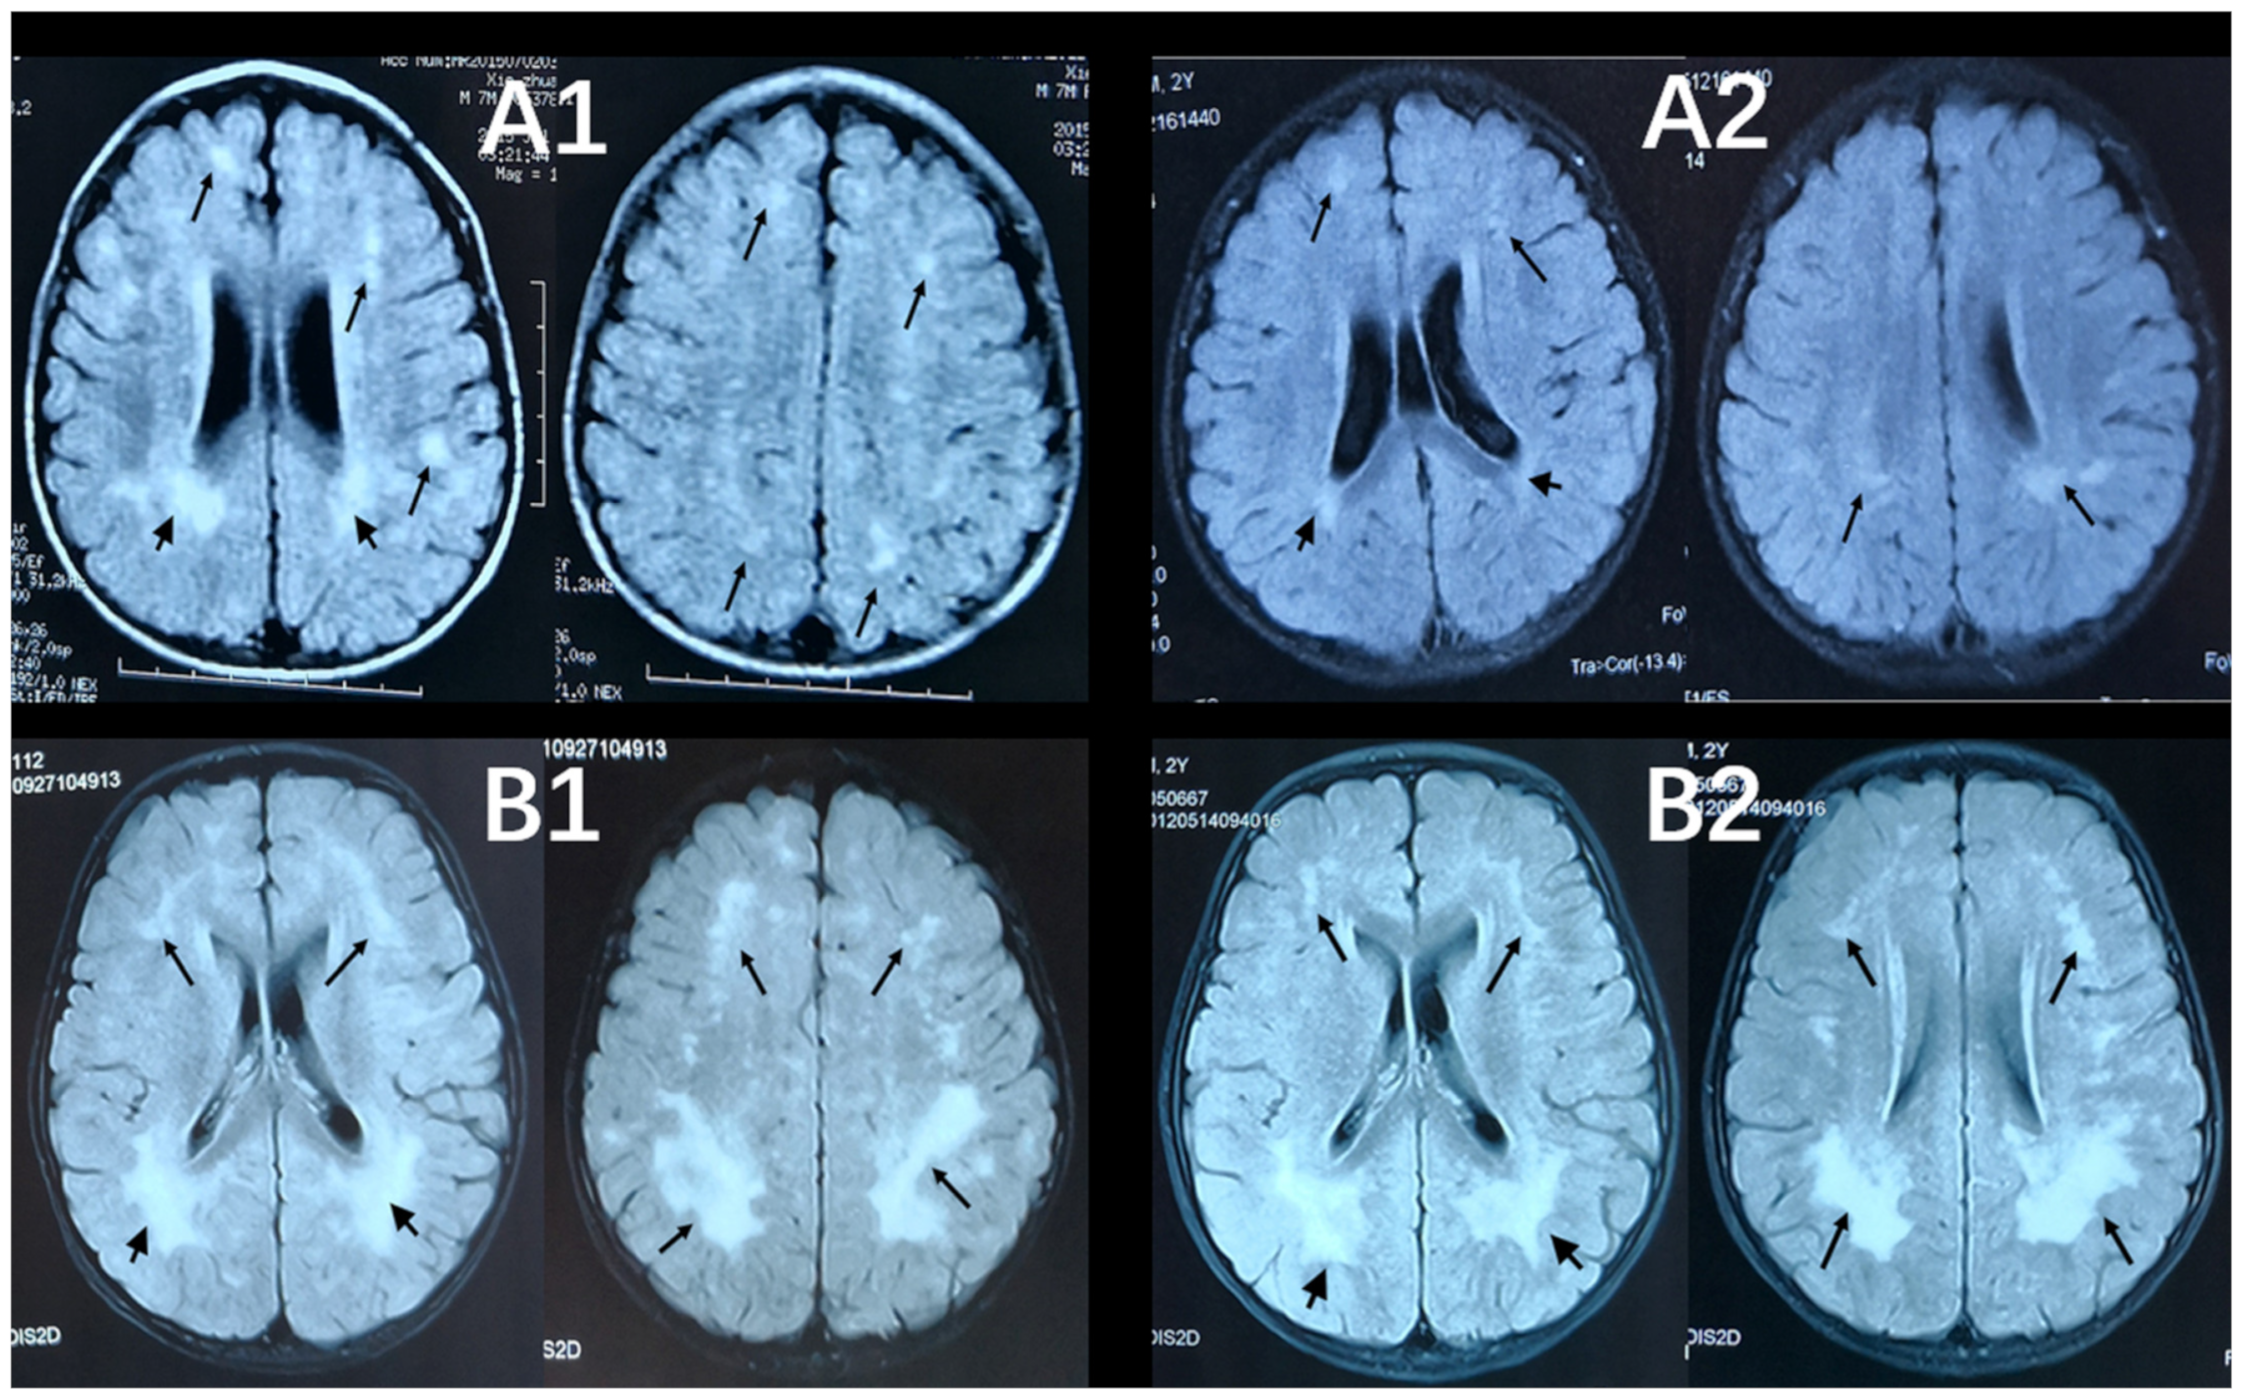

2.2. WML Evaluation: Fazekas Score

T1-weighted (T1-WI), T2-weighted (T2-WI), and T2-fluid attenuated inversion recovery sequence (T2-FLAIR) images were available for participants and interpreted by an experienced neuroradiologist. The Fazekas scale was used to assess the degree of periventricular hyperintense (PVH) and deep white matter hyperintense (DWMH) (Table 1) [17]. The total Fazekas score is the sum of the PVH and DWMH scores. Two Fazekas scores based on their two MRI scans were consistent in 42 children, and one child’s scores declined. Their second Fazekas score was used in the statistical analysis. Figure 1 shows T2-FLAIR images of two cases with annotated Fazekas scores six months apart, including the child whose score declined.

Figure 1. Axial, T2-FlAIR cerebral MRI scans six months apart of the individuals. Short black arrows point to lesions in periventricular white matter. Black arrows point to lesions in deep white matter. (A1) The first MRI scan for a 18-month-old boy showed extensive WMLs (PVH = 3, DWMH = 2, Fazekas score = 5). (A2) The second scan for the same child (24 months of age) showed improvement in WML with the Fazekas score declining (PVH = 2, DWMH = 2, Fazekas score = 4). (B1,B2) Two MRI scans of a 31-month-old (date of the second MRI scan) boy showed no obvious change in diffuse WMLs (PVH = 3, DWMH = 3, Fazekas score = 6).